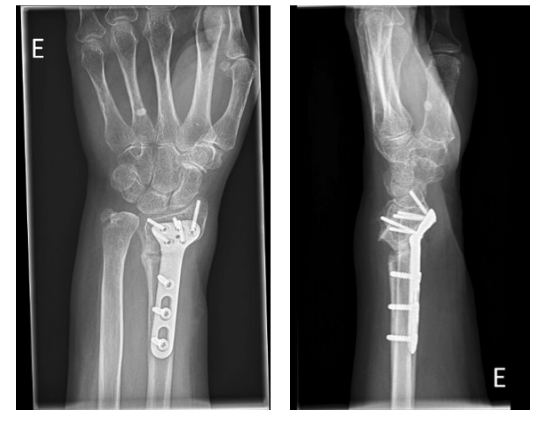

Surgery date: October 7, 2022

Immediate postoperative